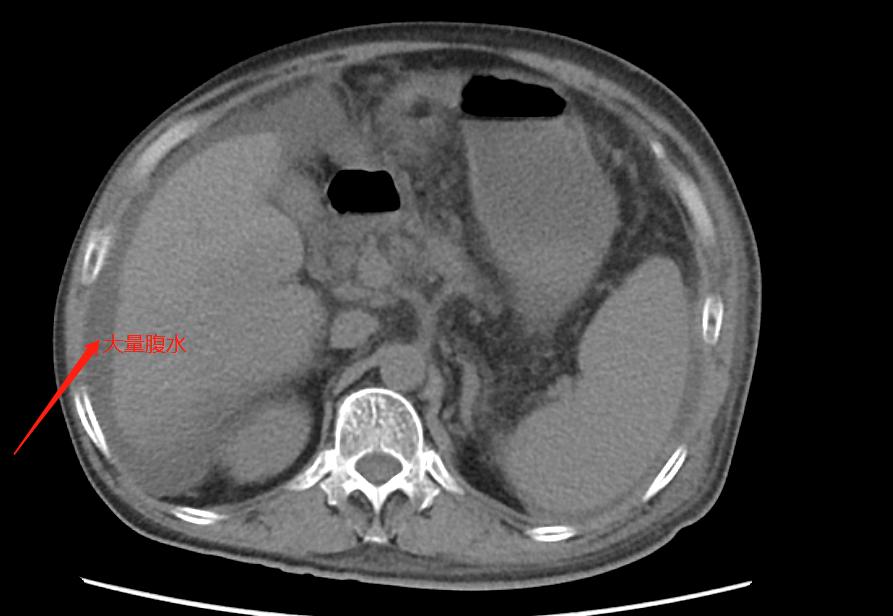

此时的他已经唇色紫褐,眼睛微突红肿布满血丝,整个腹部膨隆得像个装满水的气球,像青蛙的肚子,双下肢也是肿胀得厉害。不懂的人,看到这个样子,会以为是一个喝高了白酒的人,还是个大胖子。其实李先生并不是胖子,相比他还比较瘦小。但因为严重的肝硬化腹水,他的肚子鼓得像蛙肚,就是我们常说的“蛙状腹”。而他的面容也是比较典型的肝病面容,面色晦暗、唇色紫绀。

乙肝、肝硬化,甚至肝癌,只要提到这些名词,都会把他们串联起来,因为太多了,因为乙肝变成肝硬化或者肝癌。而李先生的肝已经因为硬化缩小了三分之一,更严重的是,他的右半肝长着一个巨大的肝癌。满肚子的腹水,带走了他身体的营养,所以他出现了严重的低蛋白血症。肝硬化、肝癌带来了身体的一系列变化,他的肾功能也开始衰竭。

一检查,不得了,严重的肝硬化、大量的腹水、巨大的肝癌。往日脾气暴躁的他,知道自己的情况变得垂头丧气。